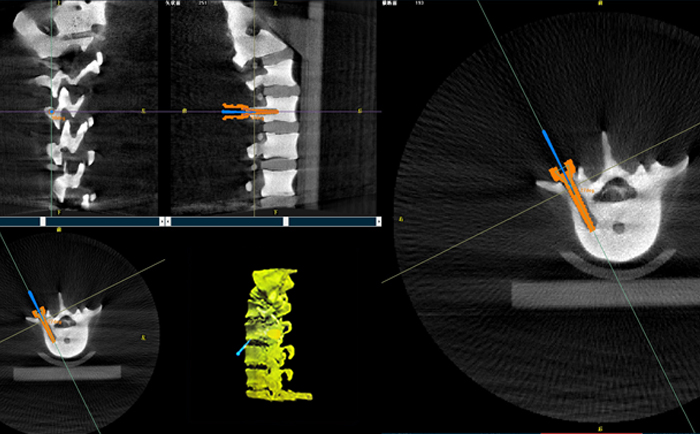

以椎弓根螺釘置入手術為例,傳統手術為了準確定位,需要將其多次進出反復選擇,增加了神經損傷與螺釘損壞的風險。但外科手術機器人可通過術前規劃把手術入路、方向、釘子深度都規劃好,基本做到一步到位,讓手術更加安全。

手術開始前,外科手術機器人與3D C形臂對患者的患處進行了一次掃描,做到“知己知彼”;接著電腦系統為每一顆螺釘設計出前進的路徑;隨后,“穩如泰山”的機器人之手——機械臂,開始為每條路徑掃除障礙,猶如鋪設火車軌道;最后沿標準路徑置入螺釘,猶如火車行駛在車軌之上,最終準確置入螺釘。

普愛醫療的外科手術機器人經國家藥監局批準,作為第三類醫療器械開始上市并應用于臨床,主要用于椎弓根螺釘內固定術、經皮穿刺椎體成形術等術式(包括頸椎、腰椎、胸椎等)等脊柱外科手術。輔助準確定位植入物或手術器械,精度達到亞毫米級,尤其對微創手術、高風險手術具有明顯優勢,可有效降低手術風險、減少手術并發癥。